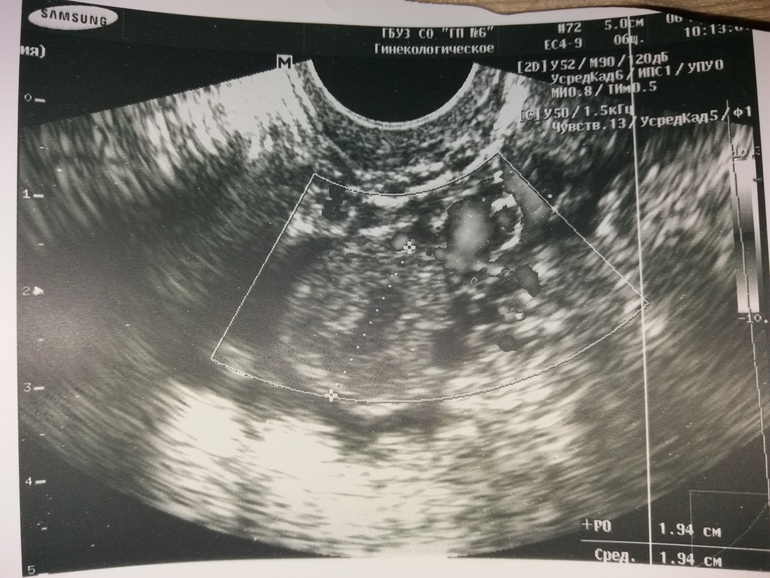

Типа если планируем беременность, то сейчас самое время. И дала вот этот снимок, сказав (вроде, не уверена потому что когда услышала что была овуляция и можно планировать Б. Возможно это знак) то что размазано это оно (если кто разбирается пояснитп пожалуйста, а то не понятно что на снимке и может я зря радуюсь?.